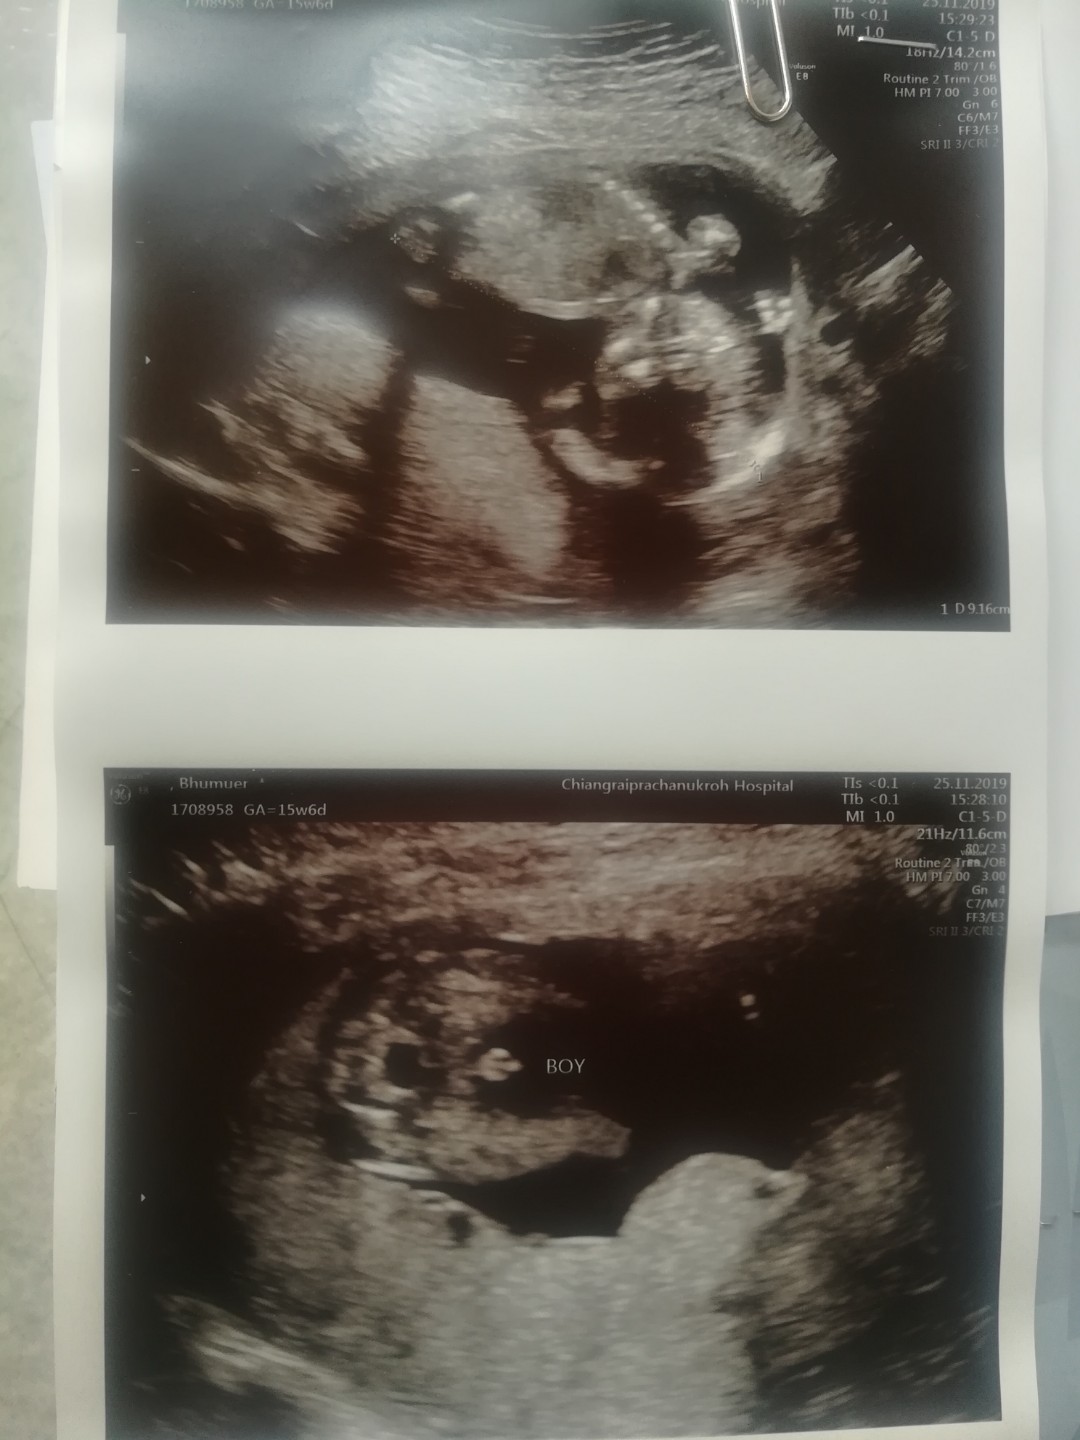

แท่งจ้ะ โด่เด่มาก😂

เจ้าหำน้อยของแม่ 🤗

โด่ชัดเจนมากคร้า555